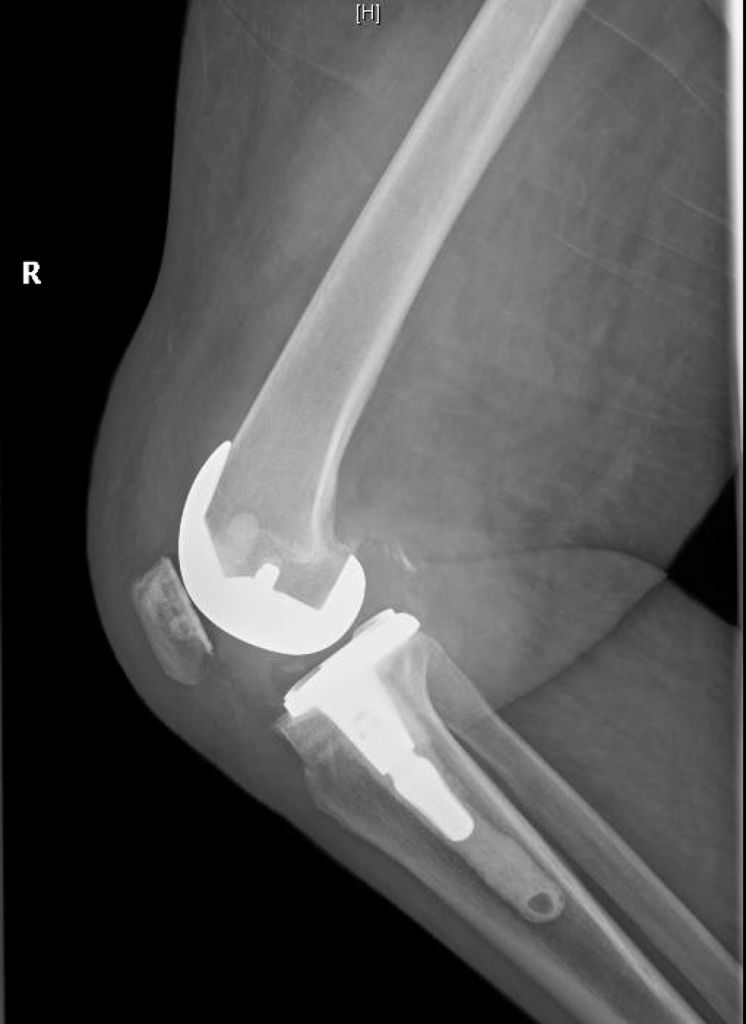

She underwent reconstructive total knee replacement, which corrected her deformity completely.

At 3 months after surgery, the patient was able to walk without pain and uses a cane for long distances only.